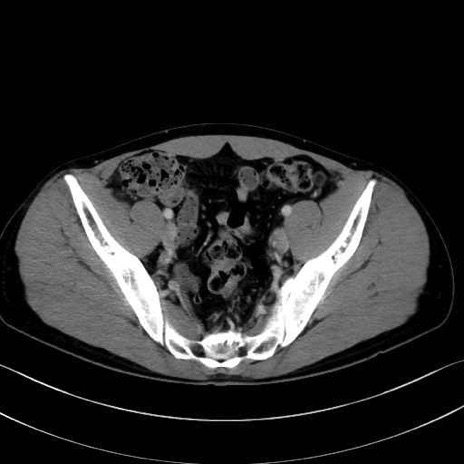

大腿筋膜張筋 (Tensor fasciae latae)